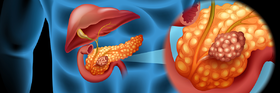

سرطان الپنكرياس

| سرطان الپنكرياس | ||

| معدل الانتشار | 393.800 (2015)[7] | |

| معدل البقاء 5 سنوات | 5%[11][17] | |

| حالات الوفاة | 411.600 (2015)[6] | |

| عوامل الخطورة | تقدم العمر، تدخين السجائر. ويمكن أن يكون من عوامل الخطورة أيضا التهاب الپنكرياس (المعثكلة) المزمن والداء السكري وتشمع (تليف) الكبد cirrhosis. معدل الحدوث أعلى في الدول ذات الغذاء الغني بالدهون، المرض أكثر شيوعا عند السود منه عند البيض. وقد ارتفع معدل الوفيات قليلا عند النساء السوداوات. | |

| العلامات المنذرة | عادة لا يوجد أي علامات منذرة حتى يستفحل المرض. | |

| الكشف والتشخيص | عن طريق الخزعة.

| |

| العلاج | من الصعب علاج الأورام التي ليست صغيرة ولا تقتصر على الپنكرياس.

| ملاحظات | * عندما يكون حجم الورم أقل من سنتيمترين ومحصورا فقط برأس الپنكرياس، وهو نهاية الپنكرياس المتصلة بالأمعاء، فإن الجراحة تجعل معدل البُقيا خمسَ سنوات نحو %20.